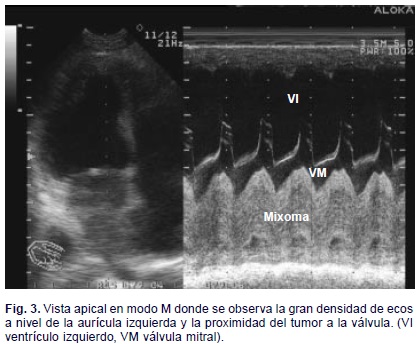

Después de 2 años de seguimiento postquirúrgico, la paciente, abandonó la consulta por sentirse bien y acudió nuevamente, 6 meses después, refiriendo disnea de esfuerzo, edema en miembros inferiores y astenia. Al examen físico encontramos escasos estertores crepitantes bibasales y ligero edema que ascendía hasta el tercio inferior de ambas piernas. La auscultación cardiovascular reveló un soplo basal II/VI, audible también en el ápex, compatible con esclerosis del aparato valvular aórtico. El electrocardiograma fue normal. indicamos exámenes humorales y radiológicos y encontramos los primeros normales, la radiografía de tórax postero-anterior no mostraba cardiomegalia, pero existía ligero edema intersticial hacia las bases y el ecocardiograma transtorácico reveló la presencia de una masa sésil de 25 x 32 mm adosada a la cara izquierda del septum interauricular que ocupaba alrededor del 60% de la cavidad auricular izquierda (Figs. 1, 2, y 3).